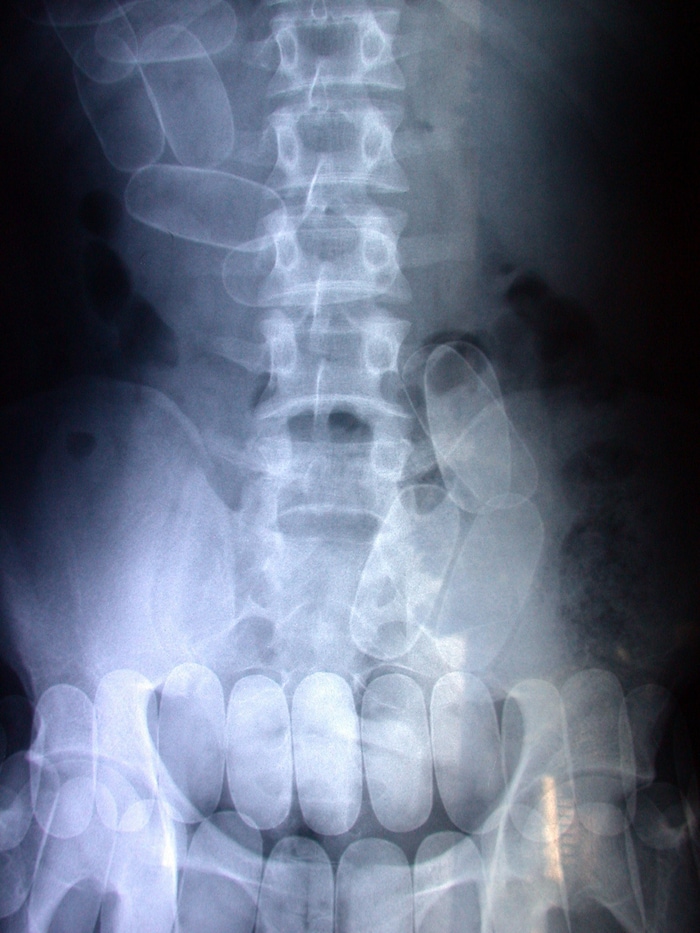

Die Kapseln – hier ein anderer Fall – sind auf dem Bild eines Computertomgrafen zu erkennen.

Die Kapseln – hier ein anderer Fall – sind auf dem Bild eines Computertomgrafen zu erkennen.(Bild: Andi Schiel)

Computertomografie machte Kapseln sichtbar

Ergebnis: Er hatte 24 Kunststoffkapseln geschluckt, die im Darmtrakt zu sehen waren. Zwei Wochen saß er dann in einer Zelle für „Bodypacker“, wo alle Ausscheidungen gesammelt werden. Irgendwie gelang es dem erfahrenen Häftling, die 240 Gramm zu entsorgen – oder gar selbst zu schnupfen?